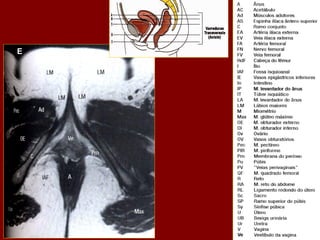

PB    Corpo do pâncreas               R         Costela                      RP    Pelve renal

PC    Confluência portal              RA        Músculo reto do abdome       RPV   Veia porta

PF    Gordura perirrenal              RC        Pilar direito do diafragma   RRA   Artéria renal direita

PH    Cabeça do pâncreas              RF        Gordura retroperitoneal      RRV   Veia renal direita

PS    Músculo psoas                   RG        Glândula supra-renal dir.    RU    Ureter direito

PT    Cauda do pâncreas               RHV       Veia hepática direita        S     Processo espinhoso

PU    Processo uncinado do pâncreas   RIL       Lobo inf. do pulmão dir.     SA    Artéria esplênica

PV(R) Ramo direito da veia porta      RK        Rim direito                  SC    Medula espinal

QL    Músculo quadrado do lombo       RL        Lobo direito do fígado       SF    Flexura esq. do colo

SI    Intestino delgado                   SV     Veia esplênica

SMA   Artéria mesentérica sup.            Tc     Coto transverso

SMV   Veia mesentérica sup.               TVP    Processo transverso

Sp    Baço                                Xp     Processo xifóide

St    Estômago

G H PB Corpo do pâncreas R Costela RP Pelve renal PC Confluência portal RA Músculo reto do abdome RPV Veia porta PF Gordura perirrenal RC Pilar direito do diafragma RRA Artéria renal direita PH Cabeça do pâncreas RF Gordura retroperitoneal RRV Veia renal direita PS Músculo psoas RG Glândula supra-renal dir. RU Ureter direito PT Cauda do pâncreas RHV Veia hepática direita S Processo espinhoso PU Processo uncinado do pâncreas RIL Lobo inf. do pulmão dir. SA Artéria esplênica PV(R) Ramo direito da veia porta RK Rim direito SC Medula espinal QL Músculo quadrado do lombo RL Lobo direito do fígado SF Flexura esq. do colo SI Intestino delgado SV Veia esplênica SMA Artéria mesentérica sup. Tc Coto transverso SMV Veia mesentérica sup. TVP Processo transverso Sp Baço Xp Processo xifóide St Estômago